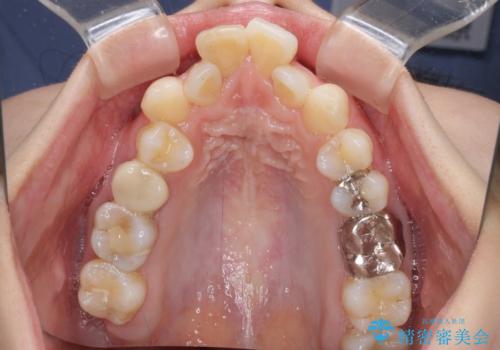

上下の咬み合わせは上顎歯列全体が歯1本分前にずれている状態であり、さらに上顎歯列はV字型に尖っていたため、上下前歯は全く接触していない状態でした。

上顎左右第一小臼歯を抜去して、ワイヤー装置にて口元の突出感を改善するよう矯正治療を行うこととしました。